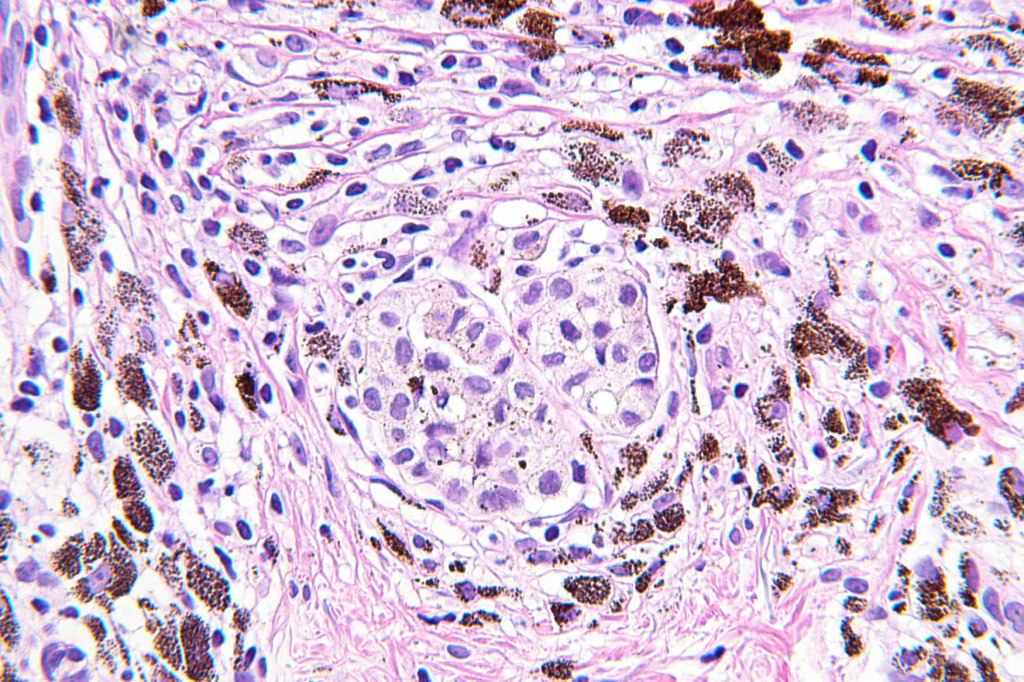

•May affect the tumor in part or whole

•Enlarged cells with copious eosinophilic, foamy or clear cytoplasm (some authors include melanoma with clear cell change in the same category)

•Variable pigmentation

•Nuclei vesicular or hyperchromatic

•Pleomorphism is not generally marked and indeed can be very subtle

•DPAS granules

•Thought to be a result of abnormal or degenerative melanosome change